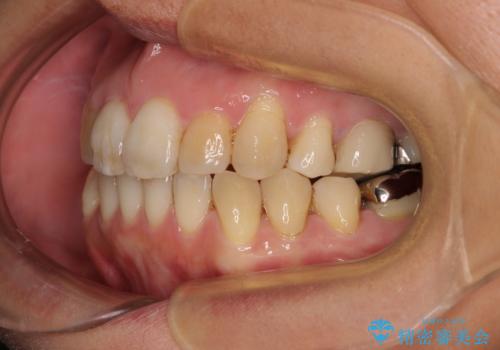

舌のトレーニングをしっかりと行ってくださり、10ヶ月で希望通りの歯列となりました。

日頃から飲まれる飲み物の影響で着色しやすいため、来院の度に着色除去のクリーニングも行っていました。